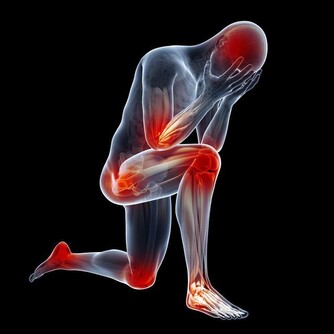

經過勞累、情緒激動、飽食、寒冷等情況下發生的心前區或胸骨後悶脹、疼痛,每次持續數分鐘,提示很可能是心絞痛。當心絞痛發作時,由於心肌缺血,可發生各種心律失常,常伴有心悸、脈搏間歇等表現。

心肌梗死是由冠狀動脈分支血管斑塊突然破裂導致的急性閉塞所致,常伴有長時間(一般超過30分鐘)的胸悶、胸痛等症狀,有的還會出現上腹疼痛、噁心、嘔吐等,嚴重者可發生心室纖顫,出現意識喪失、抽搐,甚至死亡。